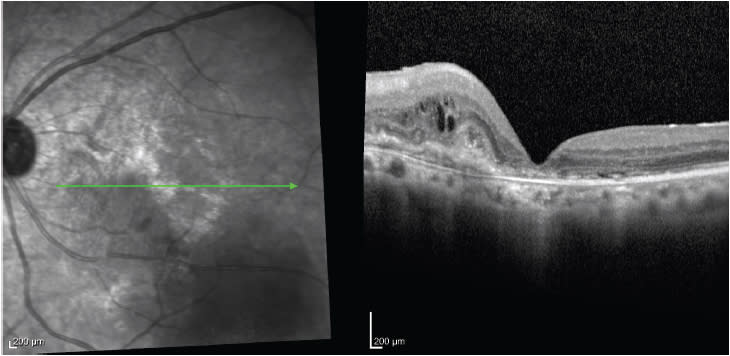

Following cataract surgery, OCT is particularly sensitive for detecting early Irvine-Gass syndrome, or pseudophakic cystoid macular edema (CME) thanks to the optical cross-section of the macula it provides, which allows for visualization of the retinal layers and its structural details. CME following cataract surgery is estimated to occur in about 4% to 40% of all cases; OCT is an easy, noninvasive way to make the diagnosis (Figure 5).

Figure 5. Spectral-domain OCT of CME after cataract surgery.

Once diagnosis of CME postcataract surgery is made, you can start treatment with topical NSAIDs and steroids, and use serial OCT images to monitor the patient’s recovery. The measurements of the central retinal thickness will help you detect worsening or resolution of macula edema. The caveat here, however, is that OCT appearance does not always correlate with visual performance.